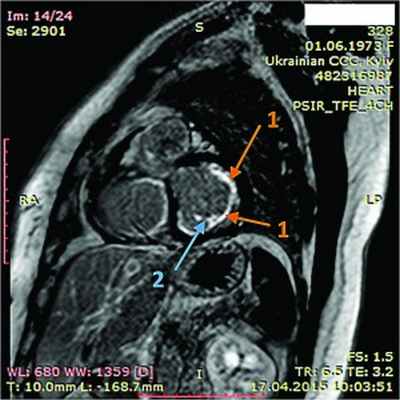

Рис. 7. Динамическая томография, боковая проекция с контрастированием эндокарда (1) и тромба ПЖ (2)

Рис. 8. Динамическая томография, поперечная проекция с контрастированием полостей и тромба в ПЖ (1), гидроперикарда по всем стенкам (2)

Рис. 9. Динамическая томография, поперечная проекция с контрастированными полостями и стенками – неравномерное утолщение миокарда желудочков (1) с двумя апикальными тромбами (2)

Рис. 10. Динамическая томография, боковая проекция с контрастированием полостей и стенок – апикальный тромб ЛЖ

Рис. 11. Динамическая томография, косая проекция с контрастированием полостей и стенок – апикальные тромбы ЛЖ

В ходе серии динамических МРТ с контрастированием (рис. 7-11) выявлены массивные пристеночные тромботические наслоения в ПЖ, апикальный тромб ЛЖ.